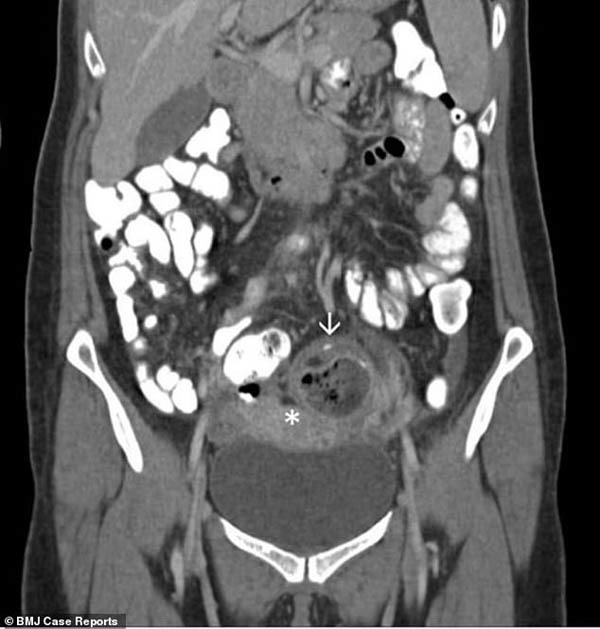

Buồng trứng phải khỏe mạnh và đạt tiêu chuẩn nhưng buồng trứng trái lại có kích thước rất lớn, lên đến 6,7cm x 5cm (kích cỡ bình thường khoảng 3cm). Và bên cạnh buồng trứng, có thêm một khối u nang có kích thước 4,7cm x 4cm.

Người phụ nữ bị u nang ở một trong hai buồng trứng (khối tối được chỉ định bởi mũi tên).